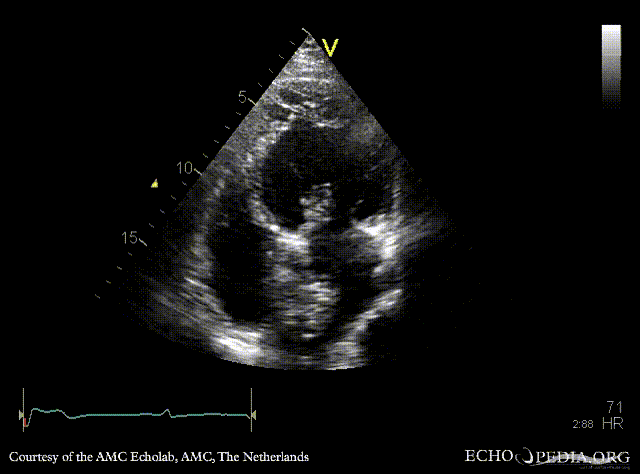

| PLAX: dilated left ventricle, myxoma in left atrium | PLAX: dimensions of myxoma |

| A4CH | A2CH |